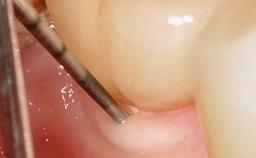

In this case, Mario Roccuzzo utilizes surgical bone regeneration treatment around implant 46 using a bone graft substitute and a connective tissue graft to resolve peri-implant inflammation, reduce the probing depths, and prevent further progression of disease.